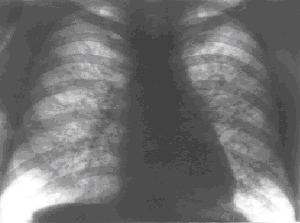

Рис. 2. Рентгенограмма грудной клетки больного саркоидозом внутригрудных лимфатических узлов и легких. Резко выраженное усиление и деформация легочного рисунка за счет диффузного уплотнения и инфильтрации интерстициальных структур, рассеянных мелких очаговоподобных теней, диффузной реакции плевры. Корни легких умеренно расширены за счет увеличения бронхопульмональных внутригрудных лимфоузлов.

Важнейшая роль в выявлении и установлении предварительного диагноза принадлежит рентгенографии; томо- и зонографию легких через плоскость корней с поперечным размазыванием теней, компьютерную томографию используют как уточняющие методы. Основу рентгенологического симптомокомплекса при саркоидозе органов дыхания составляют внутригрудная аденопатия, диссеминация и интерстициальные изменения, обусловленные явлениями альвеолита и пневмосклероза. Для саркоидоза характерно двустороннее увеличение ВГЛУ преимущественно бронхопульмональных групп, хотя в 5 – 8% случаев наблюдают одностороннее поражение, что может вызывать диагностические трудности. Симптом внутригрудной аденопатии наблюдают изолированно при саркоидозе ВГЛУ (рис.1) или в сочетании с изменениями легочной ткани при саркоидозе ВГЛУ и легких (рис.2). Легочная диссеминация характеризуется рассеянными очаговоподобными тенями диаметром от 2 до 7 мм, тяготеющими к плевральным оболочкам и сосудам и более тесно располагающимися в аксилярных зонах. Интерстициальные изменения проявляются мелкосетчатой деформацией легочного рисунка, обусловленной инфильтрацией внутридольковых интерстициальных структур. Часто наблюдают симптом "матового стекла" – диффузное снижение прозрачности легочной ткани – проявление альвеолита.